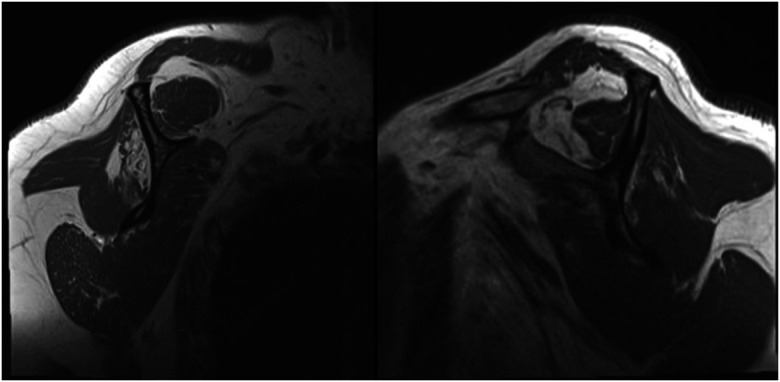

Augmentation Techniques for Rotator Cuff Repairs.

» Despite enhanced understanding of risk factors for failure and enhanced surgical repair techniques, the risk for failure of the rotator cuff to heal after surgery is still substantial.» A patient-specific approach to augmentation is essential, with decisions based on tear and patient characteristics.» Augmentation can improve repair strength and promote cellular infiltration, which collectively contribute to better healing outcomes.» Augmentation strategies may improve outcomes in rotator cuff repairs, particularly in high-risk cases; however, there is a lack of consensus among surgeons on the most effective strategies for each scenario.